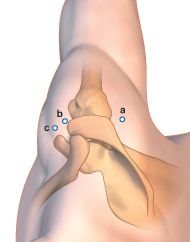

Bankart repair requires three portals, namely the posterior (P), anterosuperior (AS) and anteroinferior (AI) portals (Figure 2).

Procedure starts with the posterior portal being the viewing portal, which is established 2cm inferior and 1cm medial to the posterolateral corner of the acromion. 15-point diagnostic arthroscopy is performed using a 30 degree arthroscope. Any associated pathologies or incidental findings are noted. Anterosuperior (through the rotator interval just anterior to the anterolateral acromion) and anteroinferior (just superior to subscapularis and lateral to the tip of coracoid) portals are created by outside-in technique using an 18G spinal needle (Figure 3,4).